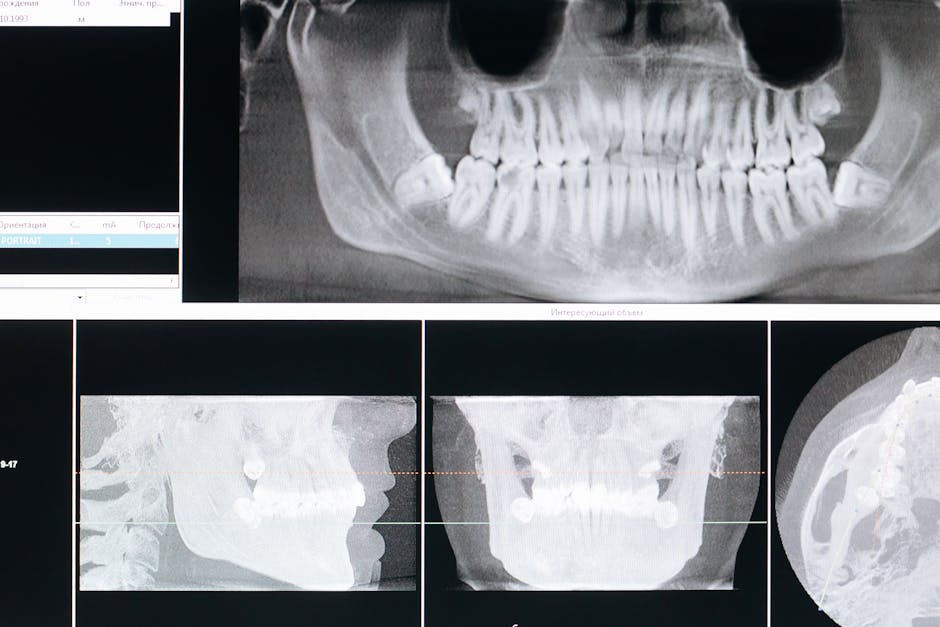

Your journey starts with an initial consultation where we get to know you and your goals. We'll take detailed digital X-rays and often CT scans to create a 3D map of your mouth. This technology helps us plan your implant placement with incredible precision – no guesswork involved.

The surgical placement happens next. Don't worry – we use local anesthesia to keep you comfortable throughout the procedure. We carefully place the titanium implant into your jawbone, then allow your gums to heal over it.

Good oral health is essential – we need your gums and remaining teeth to be healthy before placing implants. Any gum disease or decay gets treated first. Adequate jawbone density is crucial too, since the implant needs strong bone to fuse with. Our advanced CT scans show us exactly what we're working with.